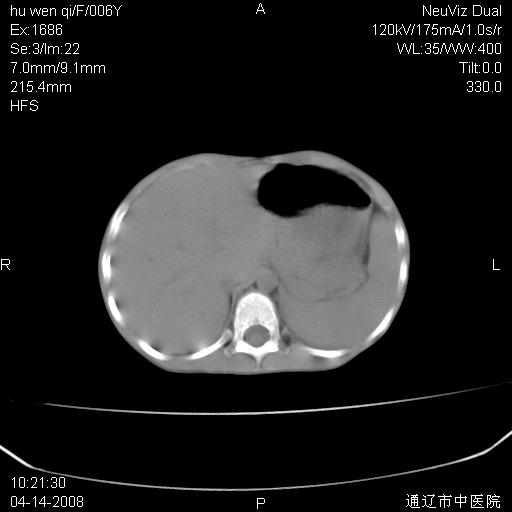

女, 6岁 ,反复咳嗽2周,近两日发热伴右侧胸痛

两肺多发似葡萄状大小不等高密度影,边界清楚,部分见薄壁空洞。左胸壁后方见局限性高密度区,边界清楚,广基与后侧胸壁相连。另示:脾大

1)考虑为:金黄色葡萄球菌肺炎;不排除两肺多发性转移瘤。2)左上腹(膈下)占位性病变;鉴别于脓肿与肿瘤之间。

左肺下叶肿块伴双肺多发大小不一结节。考虑血源性金黄色葡萄球肺炎。

谢谢各位的诊断意见,结果已经出来了,是神经母细胞瘤肺转移,原发病灶在肾,现在已进行放、化疗。

原发应该是在肾上腺